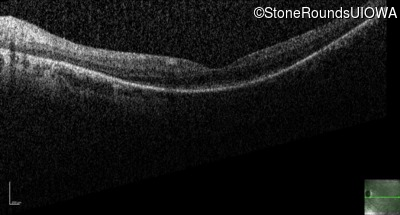

OD

OS

20/100

OCT Stack